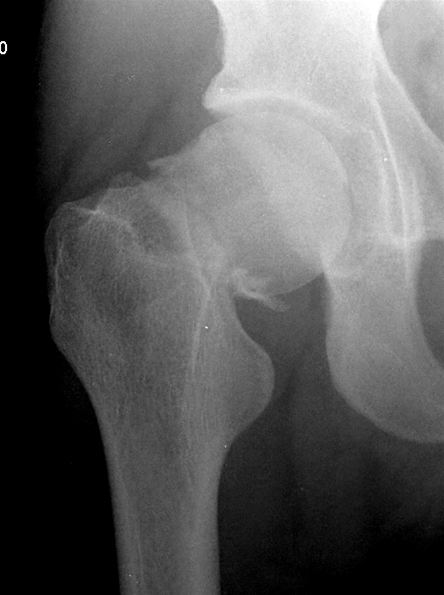

Collum femoris fraktur, forfra

Medial collum femoris fraktur med disloceret caput femoris.